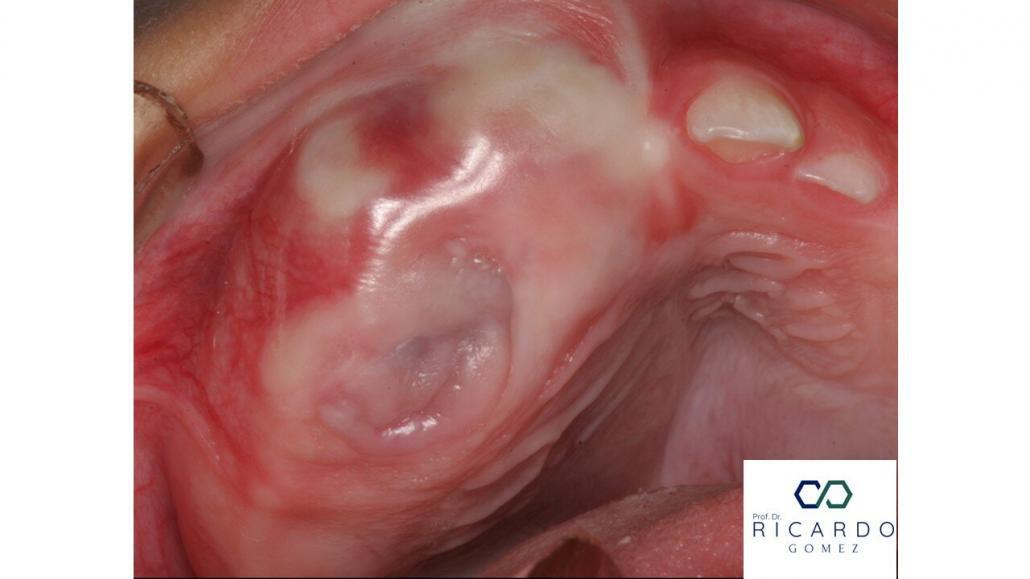

O TMNI é mais prevalente no primeiro ano de vida, principalmente entre os 3 e 6 meses. Algumas lesões são identificadas já ao nascimento. O tumor acomete mais frequentemente a maxila do que a mandíbula. A expansão tumoral pode ser clinicamente perceptível, e a mucosa que recobre a lesão pode apresentar pigmentação escura (Figura 1). Níveis elevados de VMA urinário são observados em cerca de um terço dos casos relatados na literatura.

Figura 1. Imagem clínica de um recém-nascido mostrando lesão expansiva na maxila, recoberta por mucosa com áreas de pigmentação escura (Imagem gentilmente cedida pelo Prof. Dr. Wagner Henriques de Castro).